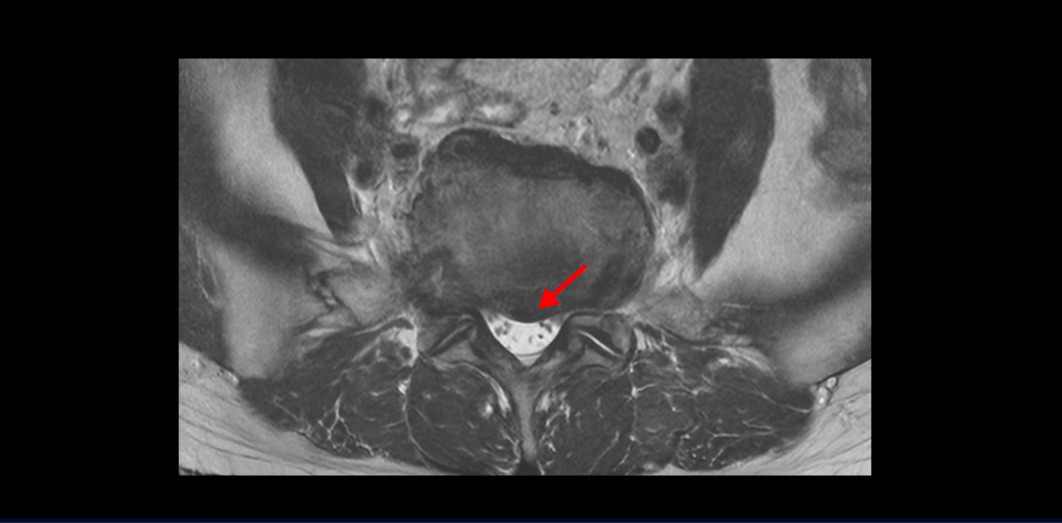

4번 5번에 심한 중심성 협착도 있습니다.

양쪽 신경 가지가 빠져 나가는 추간공도 왼쪽 오른쪽 모두 좁아져 있습니다.

이건 아주 오래된 퇴행성디스크로 보입니다. 그래서 이 환자분은 양쪽 엉덩이와 다리가 모두 저리고 아픈 게 양쪽 추간공 문제 때문일 수도 있고 중심성 협착 때문일 수도 있습니다. 퇴행성디스크 때문에 아플 가능성은 상대적으로 적어보입니다.